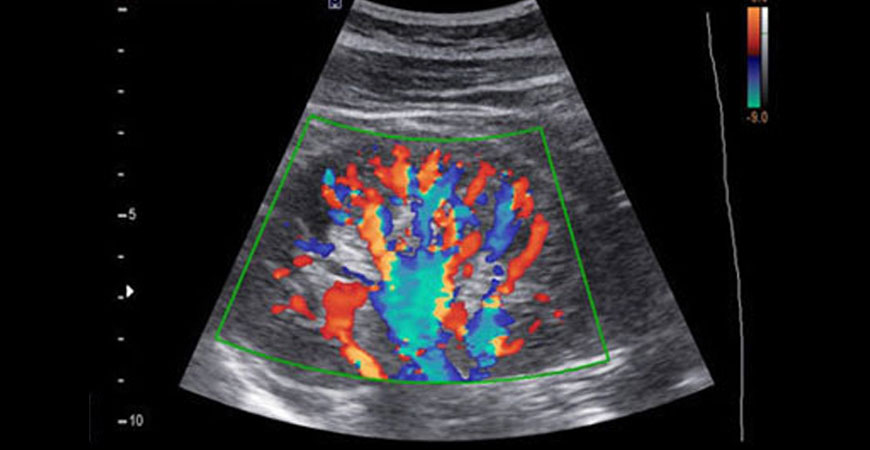

Color Doppler